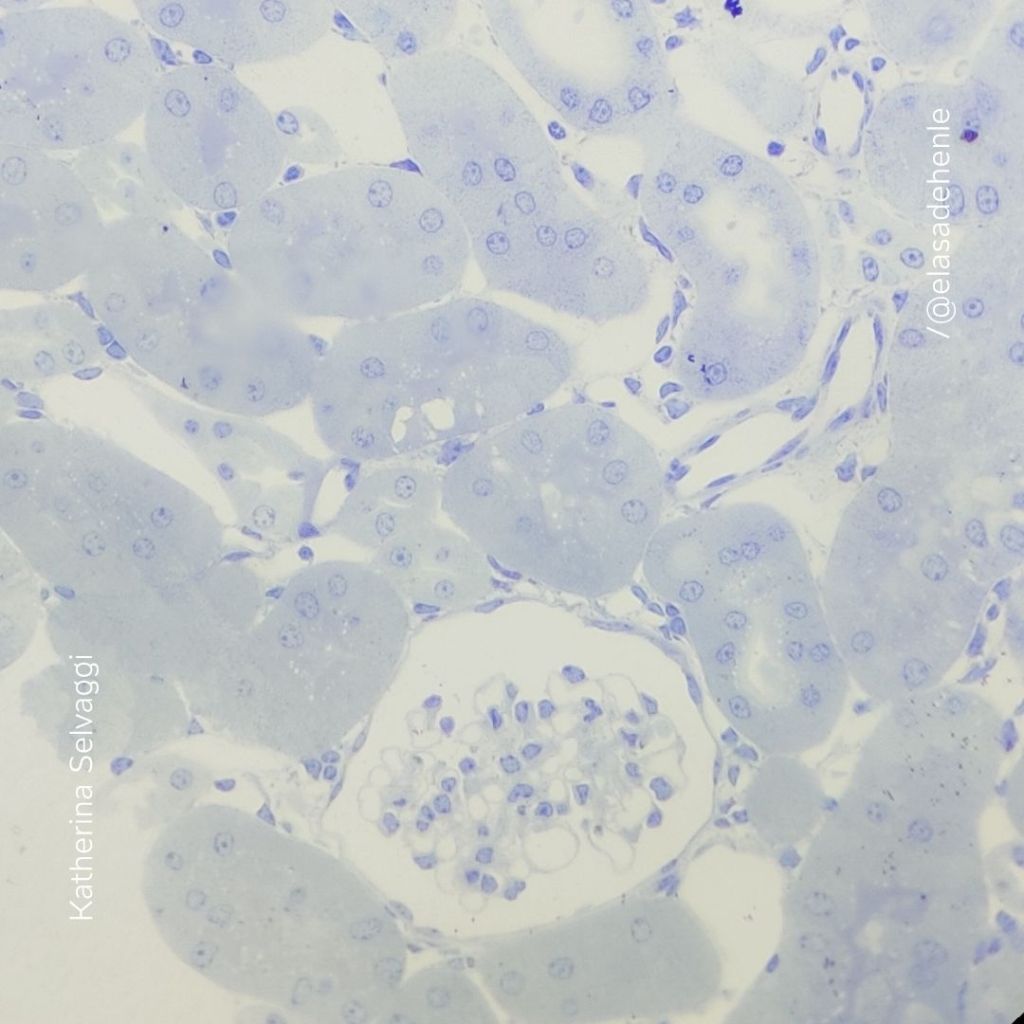

Hematoxilina y eosina

Riñón

Hospital Saint Bois